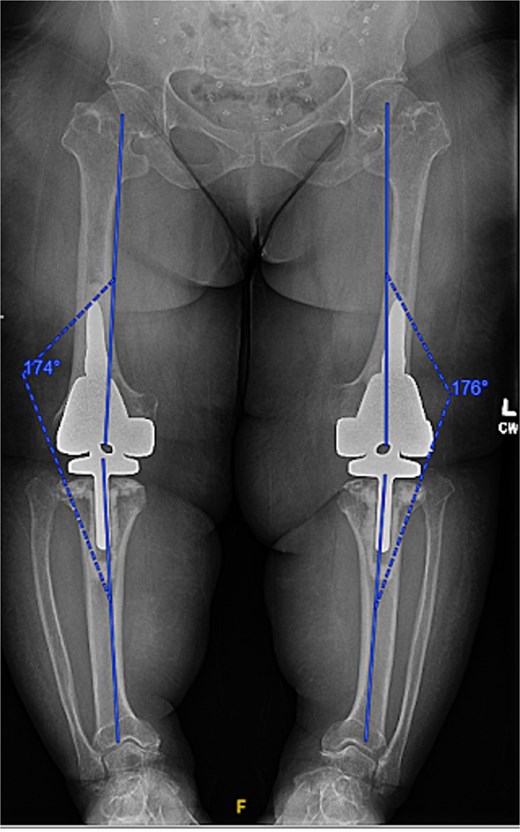

At the 2-year follow-up, the patient reported no significant pain, demonstrated a normal gait, and had active bilateral knee range of motion from 0° to 125°. There was no joint line tenderness or instability. Surveillance radiographs confirmed well-aligned and stable components with no evidence of implant failure or periprosthetic lucency (Fig. 3). At the five-year follow-up, the patient remained very satisfied with her knees and denied knee pain. On exam, her gait was slightly antalgic, but active bilateral knee range of motion remained preserved at 0° to 120°, and both knees remained stable throughout range of motion and nontender to palpation. Radiographs continued to show stable prosthetic components without evidence of implant failure or periprosthetic lucency (Fig. 4).

Two-year postoperative AP radiographs demonstrating stable, well-fixed components with appropriate alignment and no evidence of implant loosening or periprosthetic lucency.